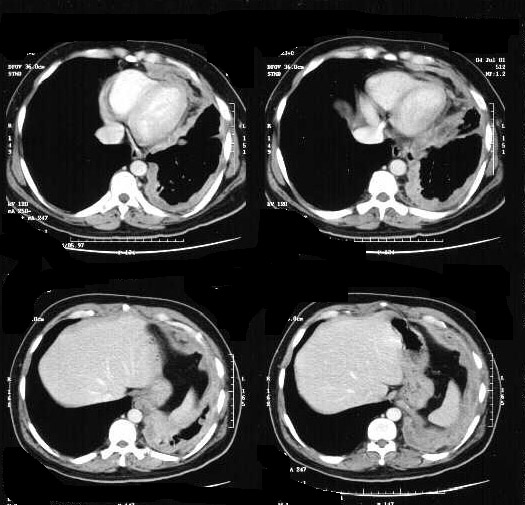

Mesothelioma

• Unilateral haziness

• Smaller left hemithorax

• Chest wall swelling

• Loss of diaphragmatic silhouette

• Blunting of costophrenic angle

• Pleural thickening / Mass